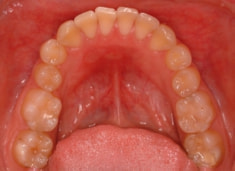

治療前